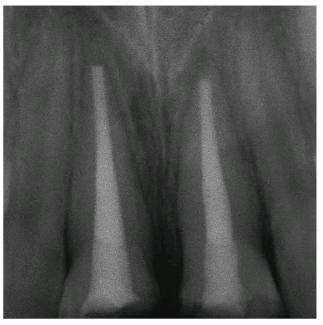

made. The two crowns were seated (Figur 323s1823d es 18-7I

and J Figur 323s1823d e 18-7K is a radiograph of the teeth at the

end of treatment.

Figur 323s1823d e 18-7K: Post-treatment radiograph of the two fractured and restored central incisors.